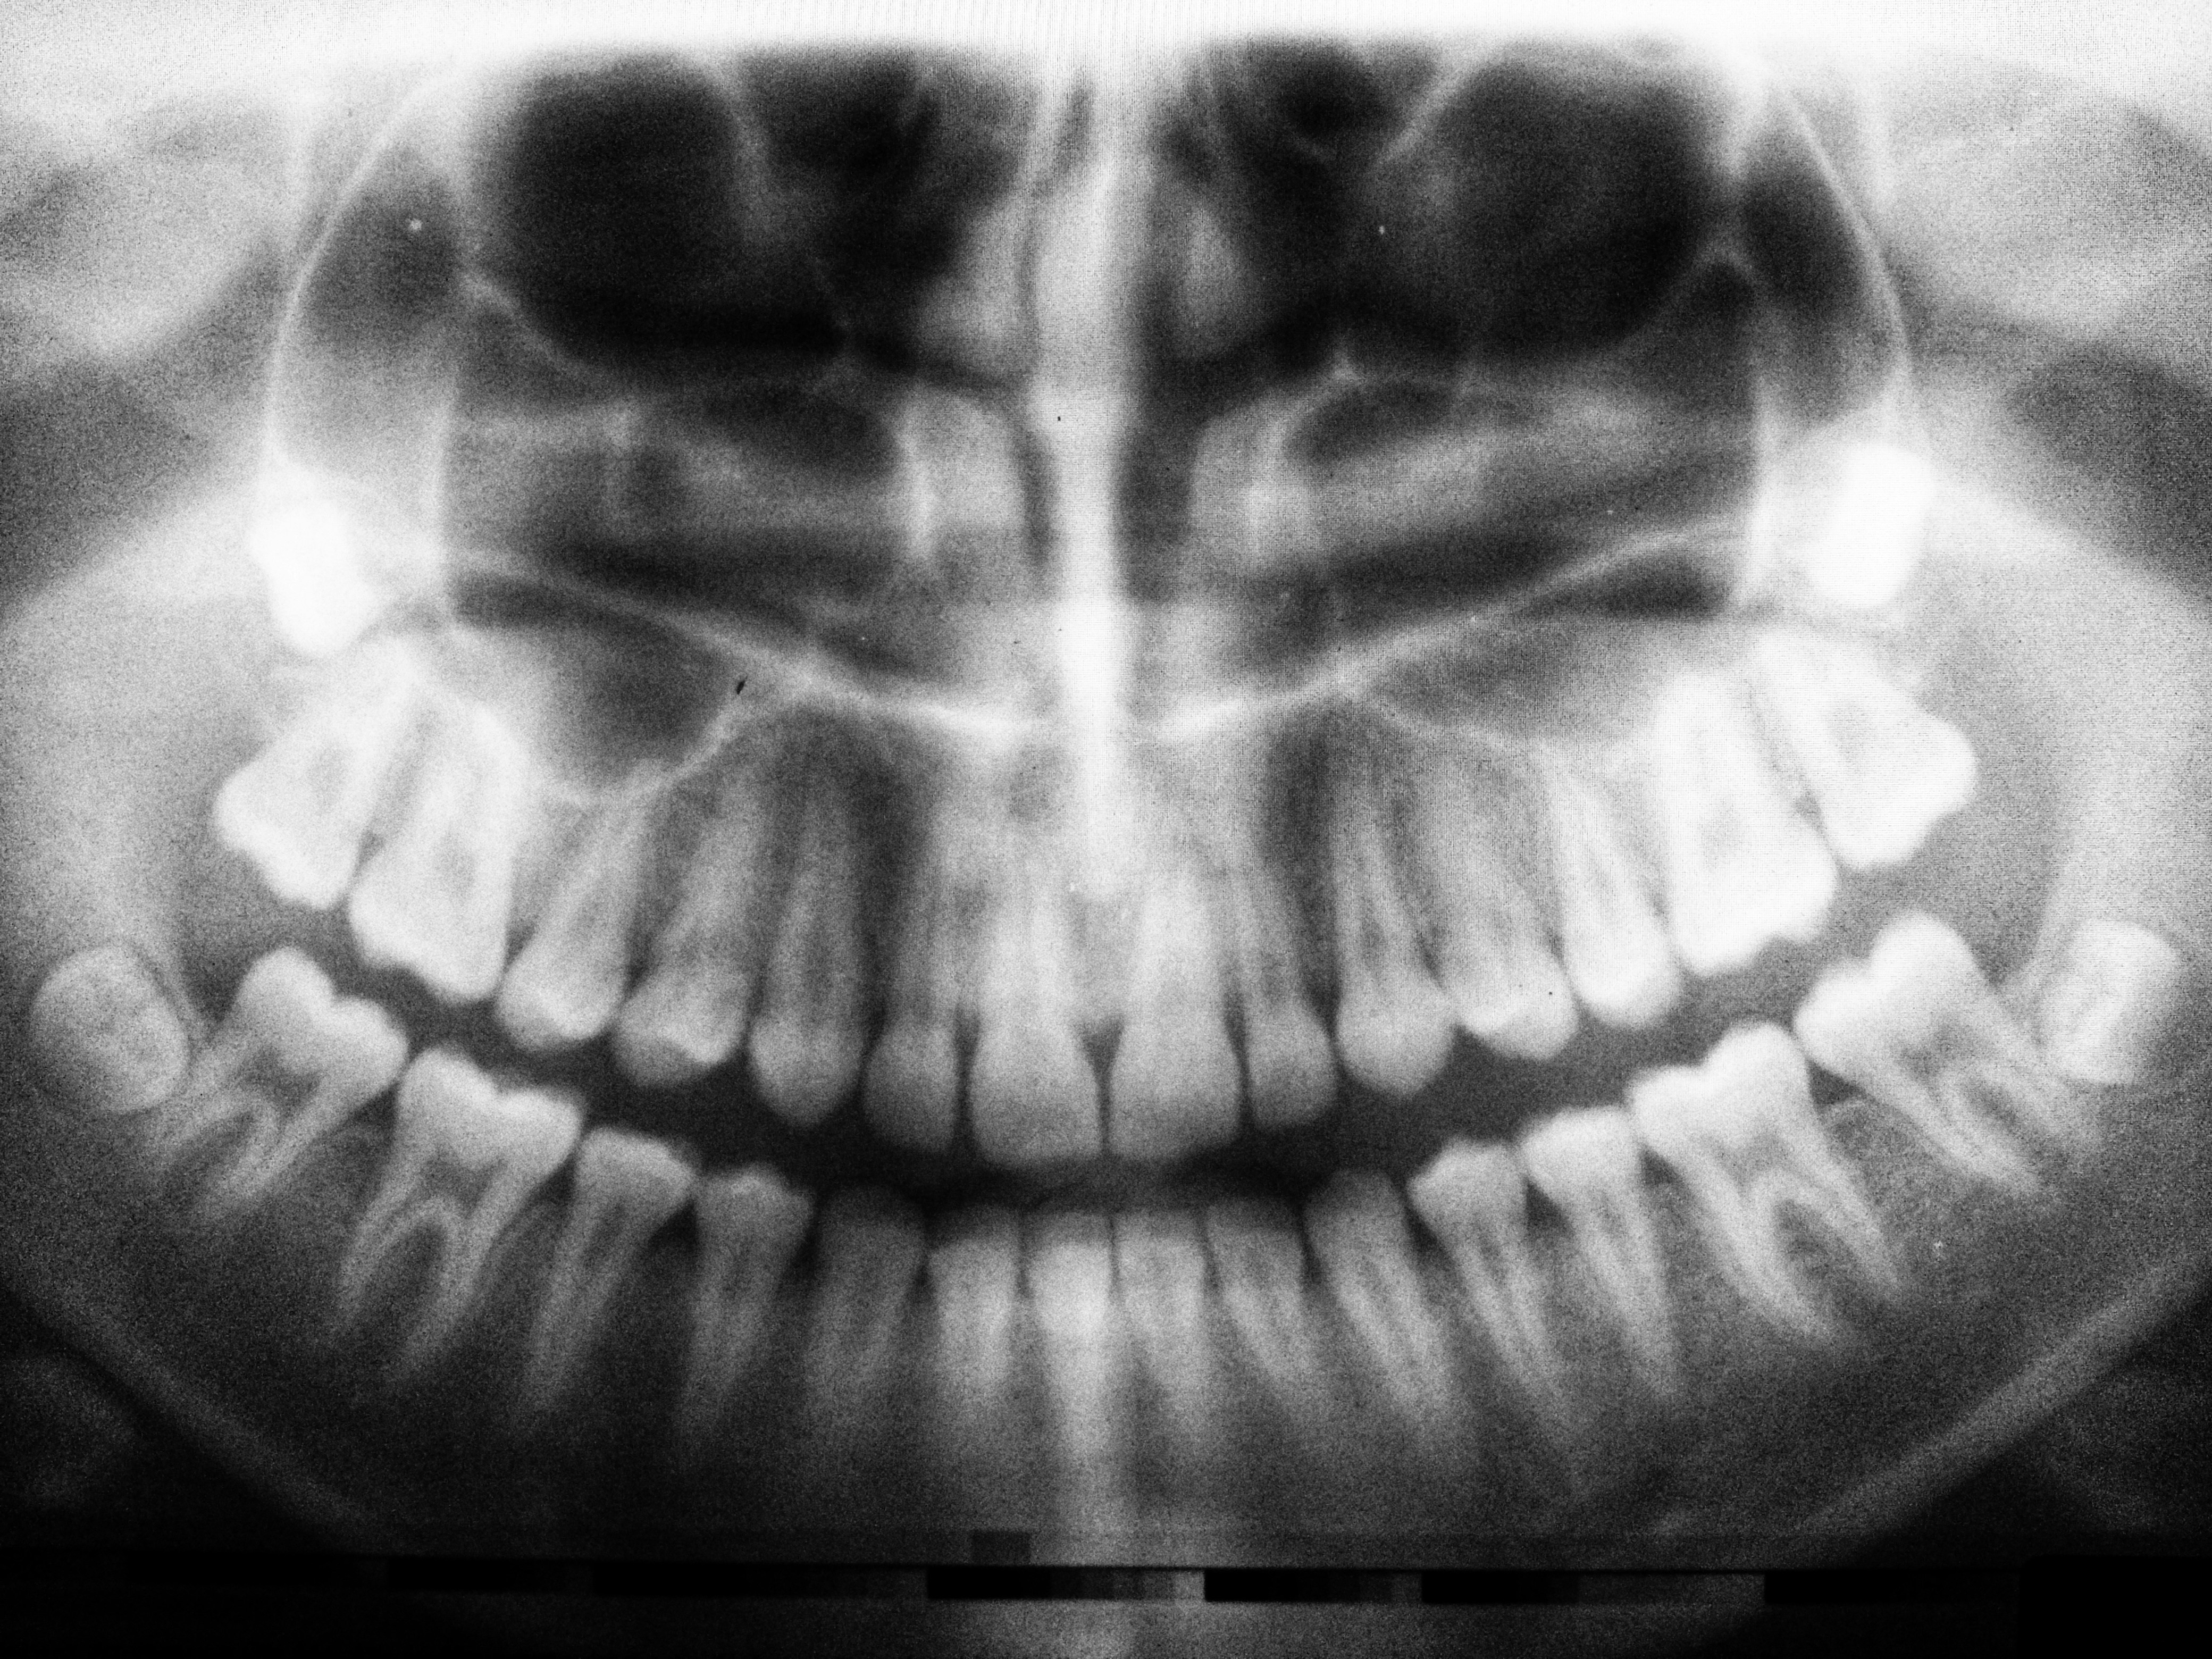

CBCT scanning has become one of the most important diagnostic tools in advanced dentistry. Unlike traditional two-dimensional imaging, CBCT provides a three-dimensional view of the jaws, bone, teeth, and nearby anatomical structures, helping clinics plan treatment more safely and accurately.

CBCT stands for cone beam computed tomography. It is widely used in implant planning, oral surgery, endodontics, orthodontics, and other situations where 3D detail can improve diagnosis and decision-making.